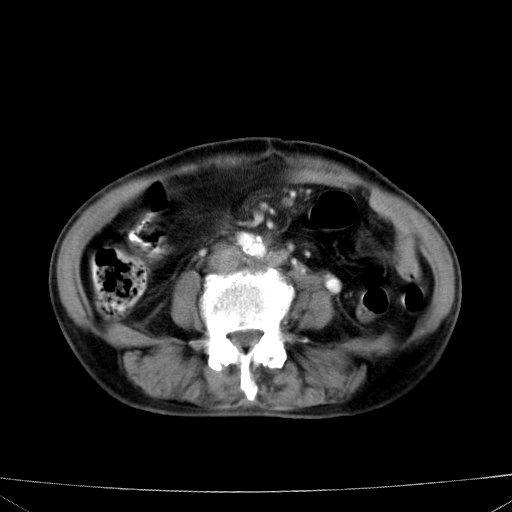

网站人气太旺!昨天的帖子就沉到海底,只好再发贴!ct18338:女 78岁,肝胆病变,已增强,再会诊!原帖链接:http://www.radida.com/bbs/forum.php?mod=viewthread&tid=50032

1)考虑胆囊癌侵犯肝脏并肝门区、腹膜后及右侧膈角后淋巴结转移。2)肝左叶近肝顶部囊肿。3)肝左叶肝内胆管结石。4)左肾近下极囊肿。